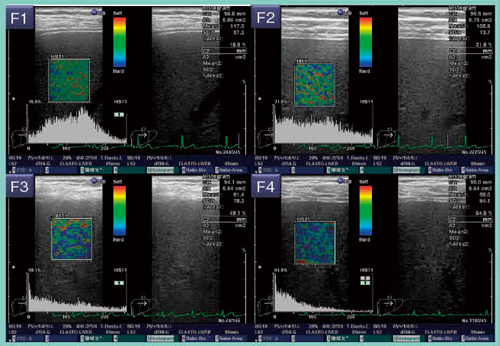

組織に圧力を加えると,硬い組織より軟らかい組織の方が大きくひずむ。Strain imagingのひとつの方法であるRTEは,相対的に変位を空間微分してひずみ量を算出し,硬い部分を青く,軟らかい部分を赤く,256階調でリアルタイムに表示することができる(図1)。

図1 RTEの原理と肝での測定方法

C型慢性肝炎の症例では,肝線維化が進行するにつれて青い領域が増え,テクスチャの乱れが生じることがわかる(図2)。藤本らも,青い領域をスコア化したLiver Elasticity Scoreと線維化に高い相関性があると報告している1)。

図2 C型肝炎症例におけるRTEと線維化の関係